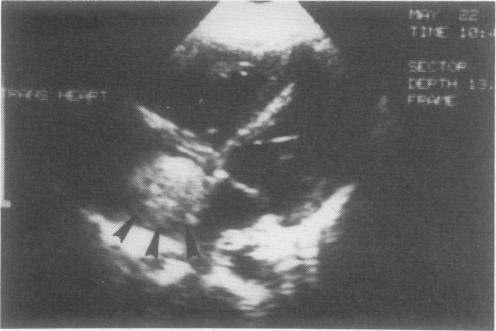

Extension of Wilms' tumor through the inferior vena cava into the heart presents a formidable clinical challenge. Excision of such a tumor without provoking emobilization may require cardiopulmonary bypass (CPB). The completeness of excision and the likelihood of tumor embolization during operation guide subsequent radiation therapy (RT) and chemotherapy. To help define these issues, the clinical records of 15 patients enrolled in three National Wilms' Tumor Studies (NWTS) who had intracardiac tumor extension (ICE) were reviewed. The median age at diagnosis was 4 years. One patient had clear cell sarcoma (CCS); the remainder had favorable histologic findings (FH). The clinicopathologic stage was stage II in one patient, stage III in eight patients, and stage IV in six patients. ICE was detected before operation in six patients, during operation in five patients, and after operation in five patients. CPB was used in 10 patients. Eleven patients (73%) had operative complications, with major intraoperative hemorrhage occurring most often (six patients). Complications occurred less often when ICE was recognized before operation (three of six patients) than when it was not (eight of nine patients). Embolization occurred in only two patients. There were no operative deaths. The patient with CCS died. Eleven of 14 patients with FH survived, with an actuarial event-free, 2-year survival rate of 86%. There were no patients in the first NWTS. Of the six patients in the second NWTS (NWTS-2), four died (67%). All nine patients in the third NWTS (NWTS-3) survived, but follow-up was shorter (median 4 years 9 months vs. 2 years 7 months). No particular surgical procedure was associated with an increased death rate. This review suggests Wilms' tumor with ICE presents a formidable surgical undertaking but has a relatively good prognosis. Embolization is an uncommon event in ICE (two patients, 13.3%), allowing a planned operative approach. Echocardiography and ultrasonography provide accurate preoperative diagnosis. And ICE should be suspected in patients with extensive vena cava thrombosis or who have hypotension or heart failure during examination or surgery.

肾母细胞瘤经下腔静脉延伸至心脏带来了严峻的临床挑战。在不引发栓塞的情况下切除此类肿瘤可能需要体外循环(CPB)。手术切除的完整性以及术中肿瘤栓塞的可能性指导后续的放射治疗(RT)和化疗。为了明确这些问题,回顾了参加三项国家肾母细胞瘤研究(NWTS)的15例有心脏内肿瘤延伸(ICE)患者的临床记录。诊断时的中位年龄为4岁。1例患者为透明细胞肉瘤(CCS);其余患者组织学表现良好(FH)。临床病理分期,1例患者为Ⅱ期,8例患者为Ⅲ期,6例患者为Ⅳ期。6例患者在术前检测到ICE,5例患者在术中检测到,5例患者在术后检测到。10例患者使用了CPB。11例患者(73%)出现手术并发症,其中最常见的是术中大出血(6例患者)。术前识别出ICE的患者并发症发生率(6例中的3例)低于未识别出的患者(9例中的8例)。仅2例患者发生栓塞。无手术死亡病例。CCS患者死亡。14例FH患者中有11例存活,2年无事件生存率为86%。第一项NWTS中无患者。第二项NWTS(NWTS - 2)的6例患者中有4例死亡(67%)。第三项NWTS(NWTS - 3)的9例患者全部存活,但随访时间较短(中位时间4年9个月对2年7个月)。没有特定的手术操作与死亡率增加相关。该综述表明,伴有ICE的肾母细胞瘤是一项艰巨的外科手术,但预后相对较好。栓塞在ICE中是罕见事件(2例患者,13.3%),允许采用有计划的手术方法。超声心动图和超声检查可提供准确的术前诊断。对于有广泛腔静脉血栓形成或在检查或手术期间出现低血压或心力衰竭的患者,应怀疑有ICE。